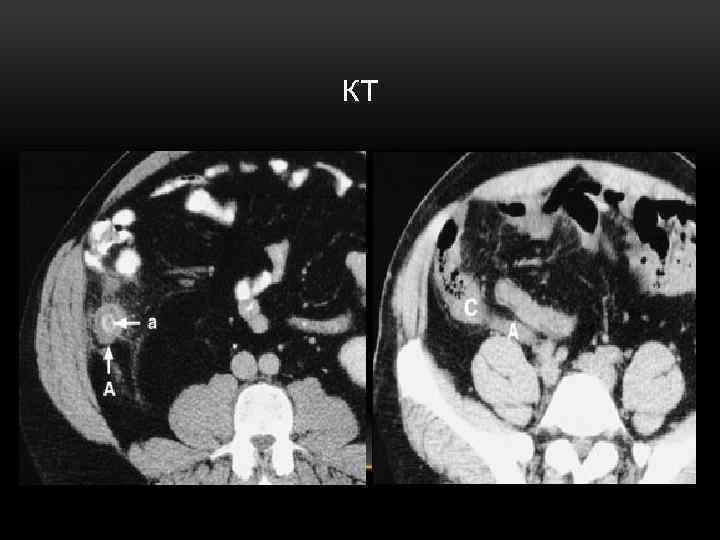

ИНСТРУМЕНТАЛЬНЫЕ ИССЛЕДОВАНИЯ • Рентгенография ОБП • УЗИ • КТ • Лапароскопия Эти методы используются в сомнительных случаях, в том числе – для дифференциальной диагностики и исключения других заболеваний, симулирующих острый аппендицит

КТ